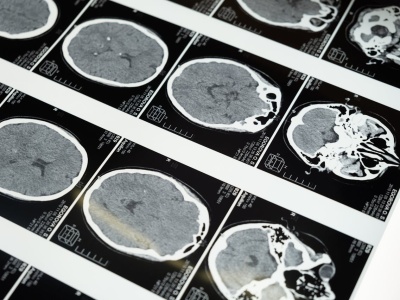

Przełomowe odkrycie: popularny lek na nadciśnienie może hamować agresywne guzy mózgu. Artykuł Jeden z najstarszych leków na nadciśnienie hydralazyna blokuje wzrost glejaka pochodzi z serwisu Alert Medyczny.